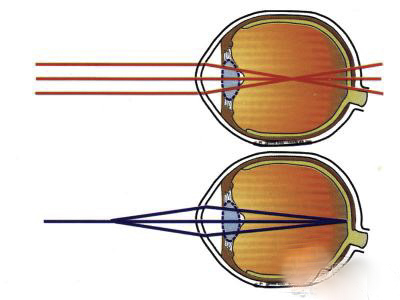

A:飛蚊症是指眼前有飄動的黑影,尤其是看白色背景的時候症狀更加明顯,同時有時候有些人會伴有閃光感,眼前一亮一亮的症狀,引起的原因主要是玻璃體液化和後脫離。絕大多數的飛蚊症都是生理性,但是有大約20%的飛蚊症,可能是病理性,具有威脅視力下降的情……

A:飛蠅症又稱飛蚊症和玻璃體混濁,是指玻璃體內出現不透明體,造成患者視物出現模糊。人出生時玻璃體呈凝膠狀態,是重要的屈光介質,正常的玻璃體隨著年齡逐漸出現液化,從而導致玻璃體混濁。此外,一切玻璃體混濁是由於病理原因所導致,例如玻璃體出血、葡萄……

A:眼前出現飛蚊的症狀往往是因為玻璃體發生了液化、變性和混濁,通常情況下玻璃體的混濁,比較多見於近視眼的人和年歲比較大的中老年人,還要特別重視的一個問題是當眼底有病變發生的時候,也會出現玻璃體的混濁、玻璃體混濁的加重,這時候眼前飛蚊的症狀需要做……